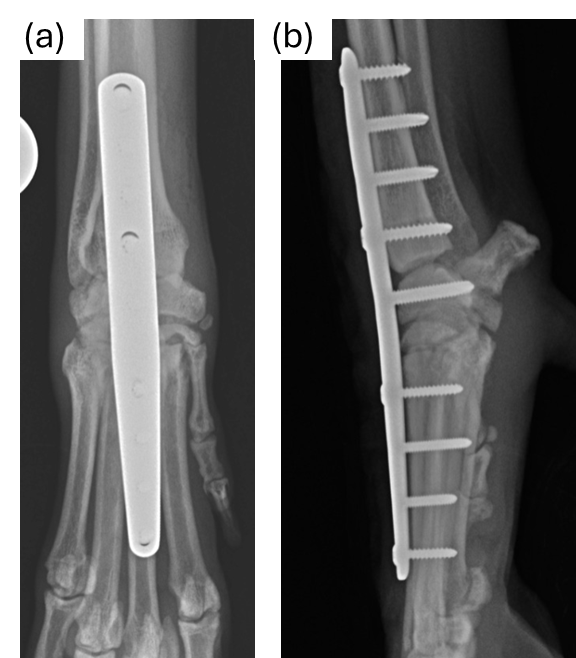

Alternatively, surgery is usually the most recommended management option and involves a salvage procedure of the affected carpus named ‘arthrodesis’, which means ‘joint fusion’, and it can be partial (only some of the joint fused) or complete (the whole joint is fused). The articular cartilage is burred away, bone graft is applied to the joint gaps and the wrist joint is bridged with an anatomic-specific bone plate and screws to provide stability (Figure 2) until the gaps are filled with new bone. Whilst the wrist joint is no longer functional, dogs adapt very well to this change by altering the way they use the limb (i.e. more elbow flexion, shoulder circumduction) and the clinical outcome is usually very good. However, arthrodesis is a particularly technical and demanding surgical procedure and complications may develop that could lead to a less optimal outcome. Therefore, a careful assessment by an orthopaedic specialist is recommended to allow the right decision-making regarding the appropriate management options.

Figure 2: Radiographic images of Anatomic-specific bone plate and screws, (a) Top view and (b) side view.